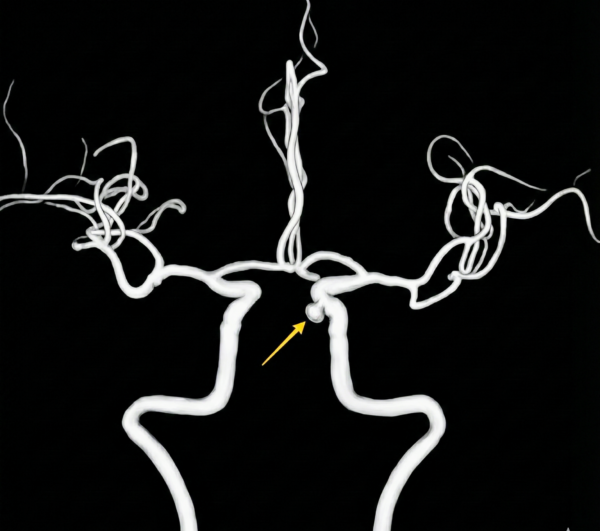

↑コブの大きさは直径3mm、根本部分は2mmほど (実際の私のMRA画像です💦)。

私の場合は、動脈瘤が、内頸動脈の海綿静脈洞部(Cavernous segment)という場所にあることから、万が一破裂しても”くも膜下出血”にはなりにくく、コブの大きさが10mm〜12mm程度になるまで破裂リスクも高くない、などのデータがあるようです。